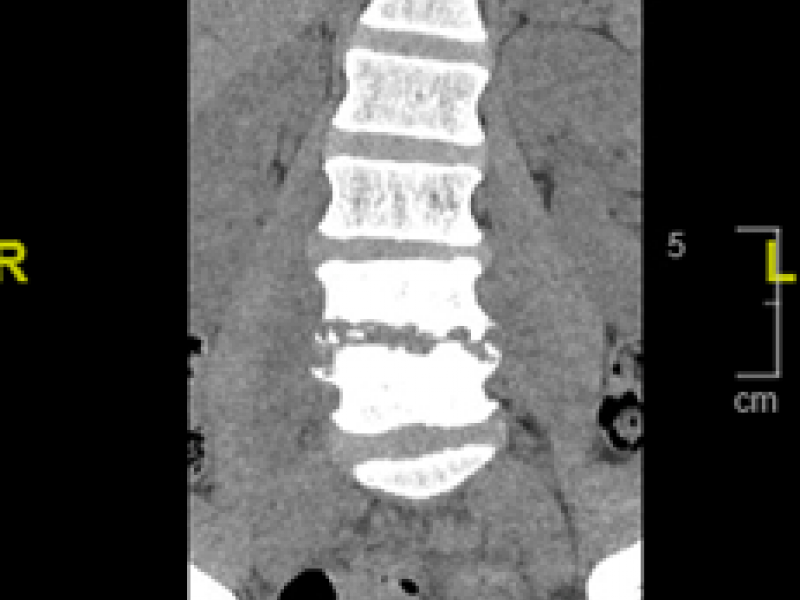

Critical Cases - Spine Emergency!

History 53 year old male with a history of IVDU and 1.5